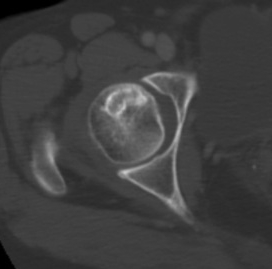

CT

Can diagnose early collapse & flattening

Crescent Sign

- subchondral collapse of the necrotic segment

- separation of subchondral plate from necrotic cancellous bone

Collapse